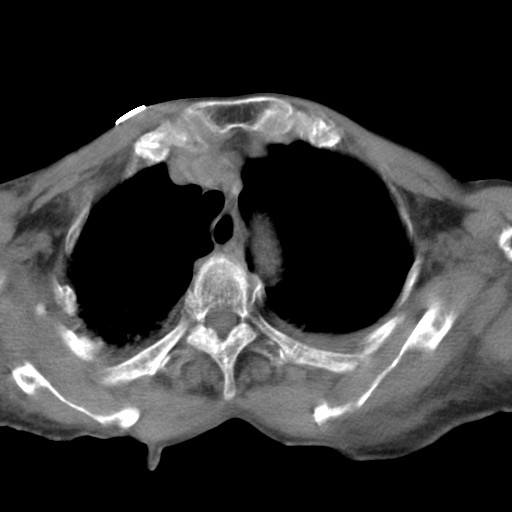

标题: CT21467:女,93岁,摔伤后检查。

女,93岁,摔伤后检查。

右肩甲骨粉碎性骨折,上传骨窗

右侧锁骨\\肩胛骨骨折、右侧湿肺,心功能不全伴双侧胸腔积液,右下肺膨胀不全,左膈破裂或食管裂孔疝,冠脉钙化,心包少量积液,请上传骨窗.

右肺炎症,心功能不全伴双侧胸腔积液,右下肺膨胀不全,食管裂孔疝,冠脉钙化,心包少量积液,左侧肋骨骨折,右肩甲骨粉碎性骨折。93岁,高寿哇!

右肺炎症,心功能不全伴双侧胸腔积液,右下肺膨胀不全,食管裂孔疝,冠脉钙化,心包少量积液,左侧肋骨骨折,右肩甲骨粉碎性骨折。